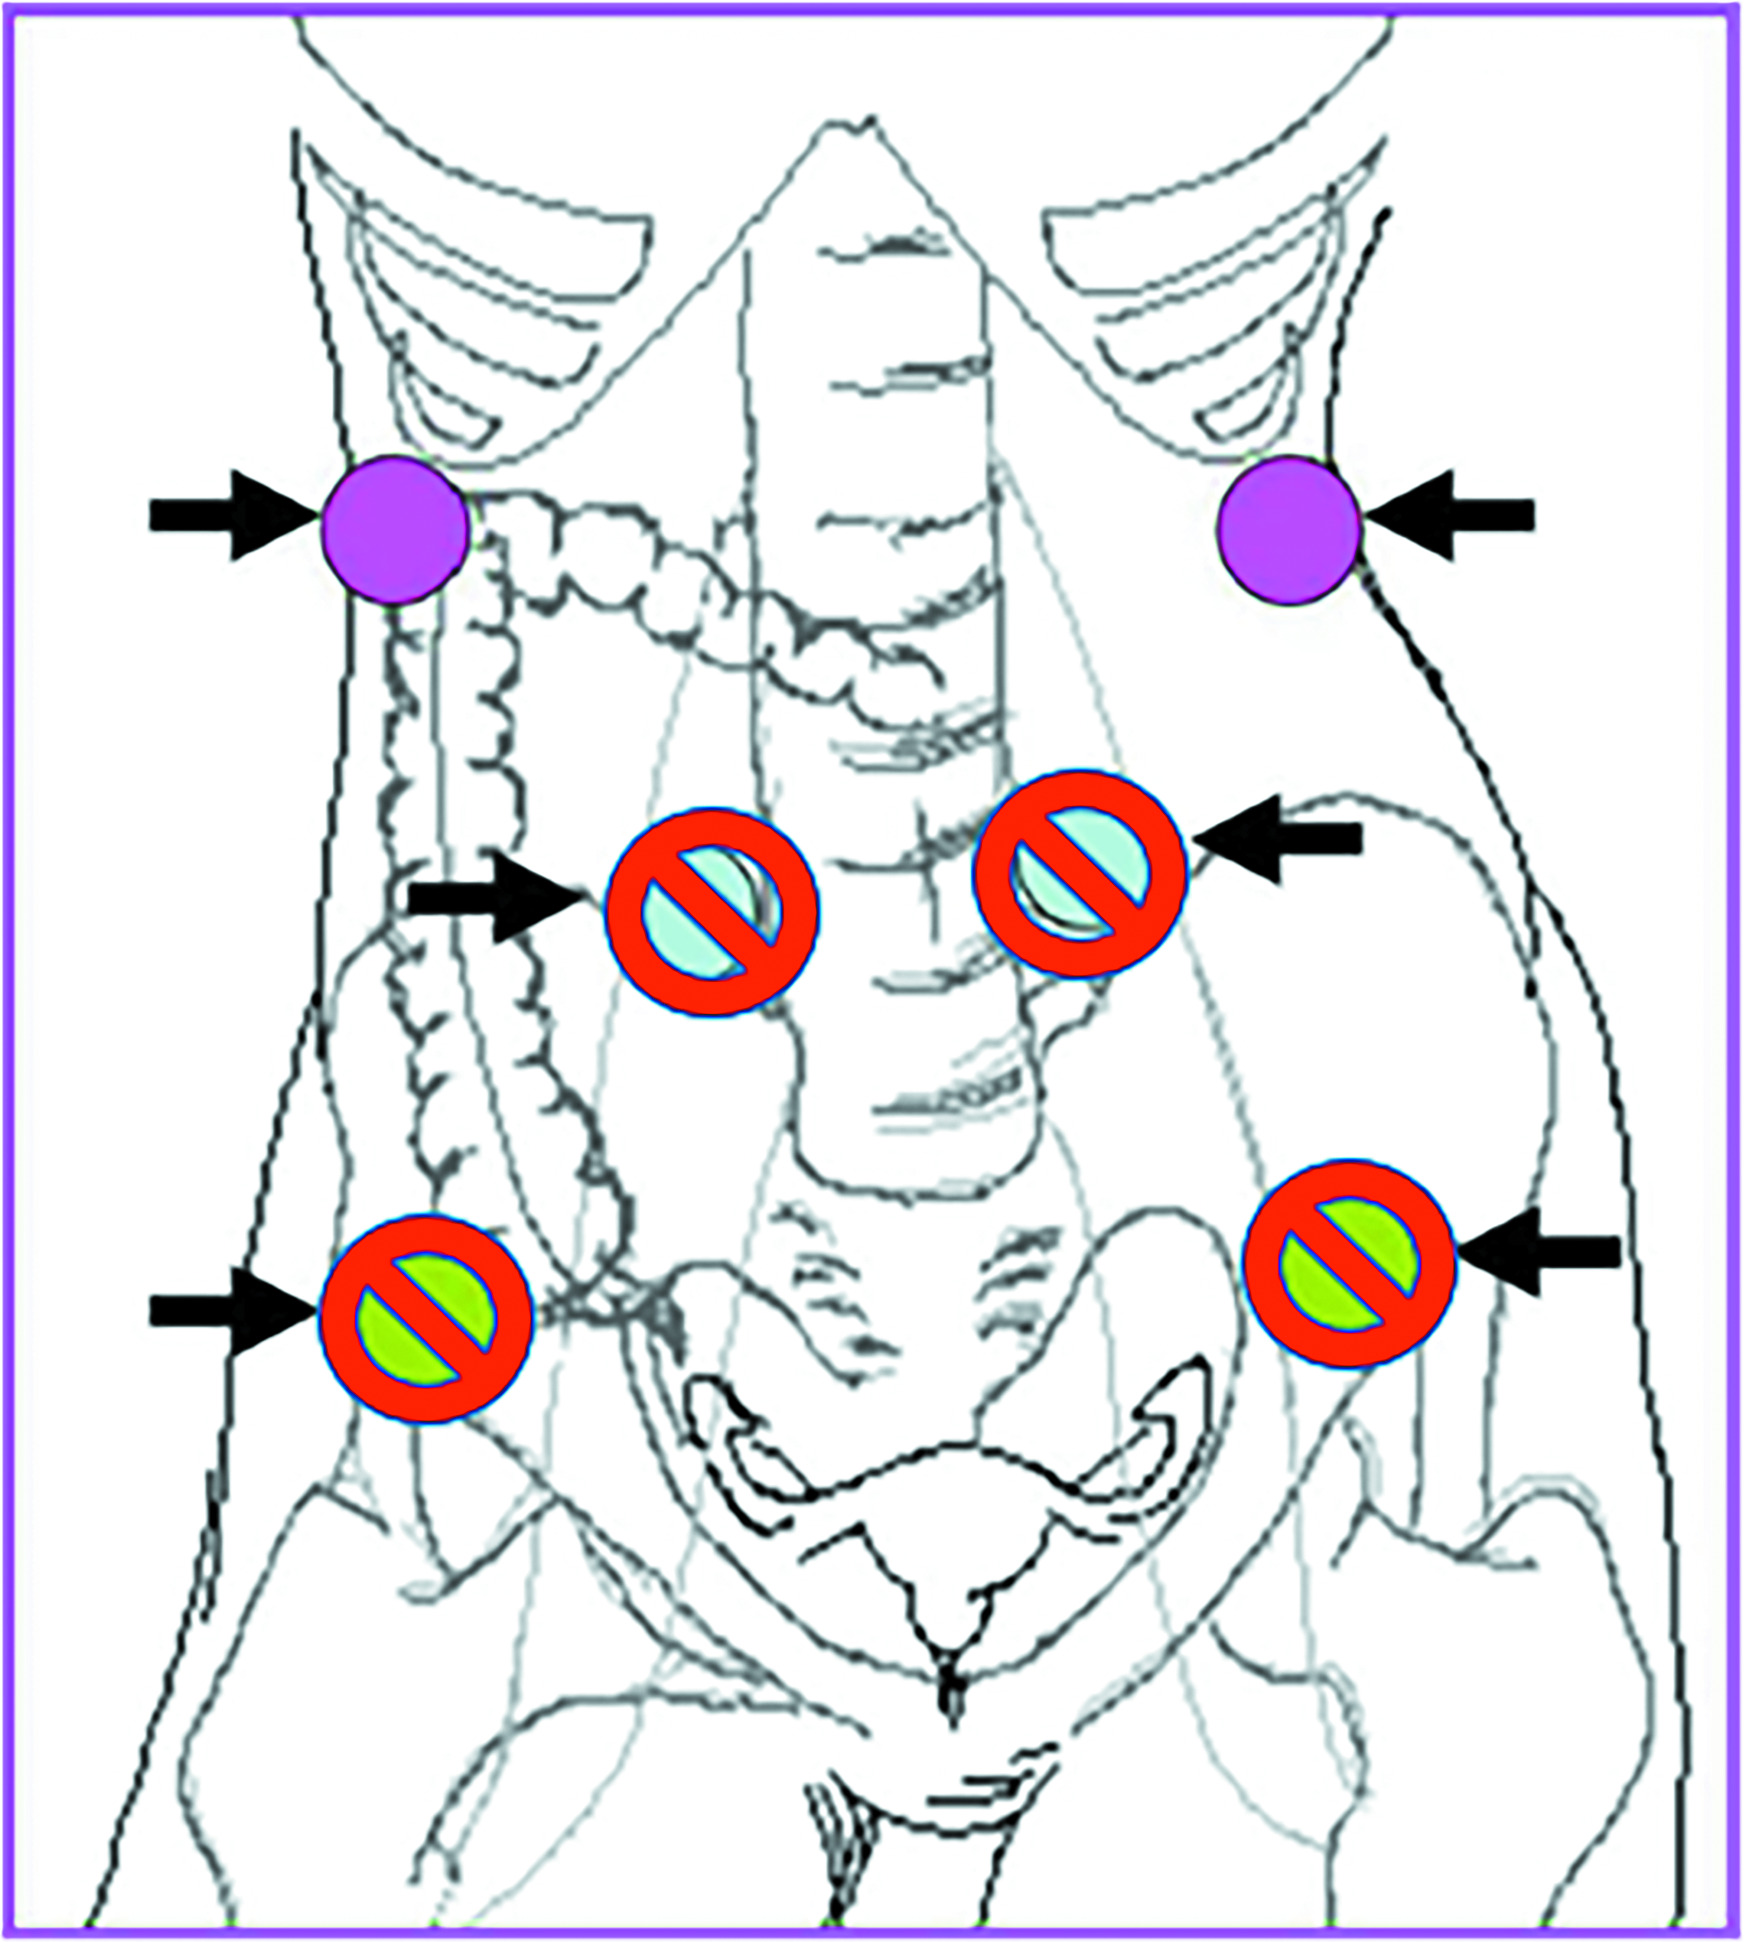

Another option for patients who do not have ovarian involvement by tumor is surgical ovarian transposition.10 With this procedure, the ovary is surgically transposed with its vascular pedicle to another location, ideally well above the pelvic brim, to minimize the radiation dose to the ovary. The procedure is most often performed laparoscopically, allowing for relatively quick recovery times. Transposition can be performed concurrently with other surgical procedures (such as pelvic node debulking, para-aortic nodal sampling, diverting ostomies, or hysterectomy/trachelectomy) or as stand-alone surgery. The ovaries should ideally be transposed at least 3 cm above the upper border of the radiation field, well above the pelvic brim and as lateral as possible (Figure 2). Although the data for ovarian transposition are somewhat limited, a 2021 Italian review of 28 manuscripts (including 699 patients with cervical cancer undergoing ovarian transposition and RT ± chemotherapy) showed that transposition was able to preserve ovarian function in 62% of patients. Ovarian preservation in these studies was defined as FSH < 10 mIU/mL, E2 > 50 pg/mL, and the presence of follicles on ultrasound. The type of treatment had implications on ovarian preservation rates as well, with an 86% preservation rate with brachytherapy alone vs a 55% preservation rate in patients who received external-beam radiation therapy + brachytherapy.11 Complication rates are typically low, with a reported rate of approximately 8.5%.12 Laparoscopic ovarian transposition is recommended due to decreased complication rates, reduced time to starting pelvic RT, and very high ovarian survival rates.13,14 Studies have shown that in women under age 40 who underwent laparoscopic ovarian transposition, ovarian function preservation rates were as high as 88.6%.15 There are no consensus guidelines on dose constraints to transposed ovaries, and ideally, the dose to the transposed ovary or ovaries should be as low as possible. However, one study looking at women treated with intensity-modulated radiation therapy after ovarian transposition showed that dose constraints of a maximum dose < 9.985 Gy, mean dose < 5.32 Gy, and V5.5 < 29.65% to the transposed ovary could be better at preventing ovarian dysfunction, especially in women under age 38.16

CT simulation can typically be performed within a week of the procedure if the abdominal wall has sufficiently deflated (after surgical insufflation with laparoscopy) for reproducible treatment planning and delivery. The surgeon should mark the location of the transposed ovary or ovaries with a surgical clip and the ovarian tissue should be contoured for dosimetric evaluation. If the ovary is high enough in the abdomen, there should be minimal direct dosing to the ovary; however, the ovary will likely still receive some radiation exposure via internal scatter. This is important to explain when counseling patients, as the risk of ovarian failure remains given the tissue’s sensitivity to radiation. Other risks associated with ovarian transposition include complications at the time of surgery, ovarian torsion, vascular injury, fallopian tube infarction, and small bowel obstruction due to postsurgical adhesions. Ovarian cyst formation is common and reported in up to 95% of patients but is unlikely related to the transposition procedure. Patients who undergo successful ovarian transposition with function retained after radiation therapy may retain viable eggs after treatment, which can later be retrieved for in vitro fertilization procedures. Ovarian transposition tends to be more successful in younger women, with the best outcomes seen in patients under age 35 (preservation rates by age: 25-30: 87.5%; 31-35: 62.5%; and 35-40: 42.9%).17 National guidelines by the American Society of Clinical Oncology and the National Cancer Comprehensive Network3,18 both recommend offering ovarian transposition to appropriately selected AYA cancer patients (Table 2) and referral to psychosocial providers when patients are distressed about potential infertility.